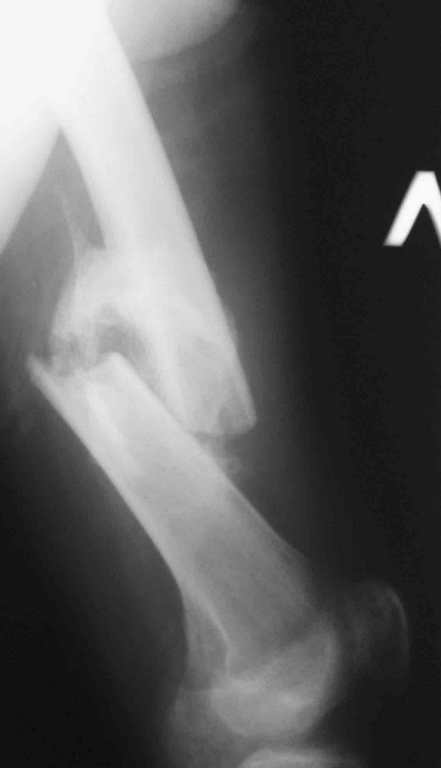

Re: 32- летний пациент с переломами обоих бедер по

Иллюстрации к сообщению